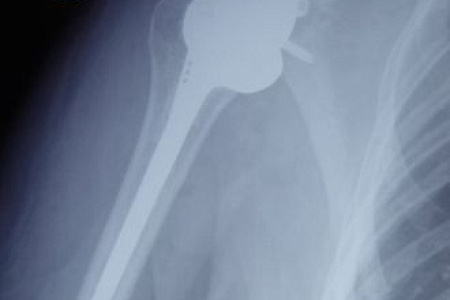

Чтобы восстановить функцию плечевого сустава, врачи травматолого-ортопедического отделения ФМБЦ им. А.И. Бурназяна ФМБА России впервые выполнили реверсивное эндопротезирование плеча. В ходе операции хирурги удалили поражённую головку плечевой кости, на место которой поместили реверсивный эндопротез – плечевой компонент протеза вогнутый, а со стороны лопатки выполнен в форме сферы. Такой тип протеза позволяет восстановить функцию сустава при дефиците мышц вращательной манжеты плеча и показывает лучшие результаты, чем другие эндопротезы.